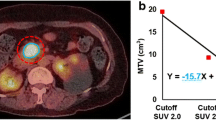

Relationships between imaging biomarkers and OS in all patients

Univariate analyses revealed that advanced stage (P = 0.041; hazard ratio [HR] = 2.041, 95% confidence interval [CI] = 1.029–4.048), low peak (P = 0.006; HR = 2.559, 95% CI = 1.315–4.981, Fig. 4a), low ADCmin (P = 0.002; HR = 2.861, 95% CI = 1.477–5.543, Fig. 4b), and high TLG (P = 0.01; HR = 3.511, 95% CI = 1.182–10.429, Fig. 4c) were prognostic factors for poor OS. In addition, a high metabolism-to-flow ratio (TLG/peak [P = 0.016; HR = 3.511, 95% CI = 1.182–10.429]) was a prognostic factor for poor OS (Fig. 4d). Cox multivariate analysis revealed that TLG/peak (P = 0.006; HR = 4.61, 95% CI = 1.565–13.582) and ADCmin (P = 0.011; HR = 0.999, 95% CI = 0.998–1) remained independent predictors of OS after adjusting for age, gender, tumor size, TNM stage, and other imaging biomarkers (Table 5).

Kaplan–Meier survival curves show that patients with low values of (a) peak or (b) minimum ADC (ADCmin) have shorter overall survival than those with high values. Patients with high values of (c) total lesion glycolysis (TLG) or (d) TLG/peak ratio have shorter overall survival than those with low values

Similarly, univariate analyses revealed that peak, ADCmin, TLG, and TLG/peak were prognostic factors (all P < 0.05). Only the final factor was significant in multivariate analyses after adjustment for age, gender, tumor size, TNM stage, and other imaging biomarkers (P = 0.013; HR = 4.573, 95% CI = 1.373–15.236) (Table 6). Therefore, TLG/peak was the best predictor for OS in patients who did not receive curative surgery.